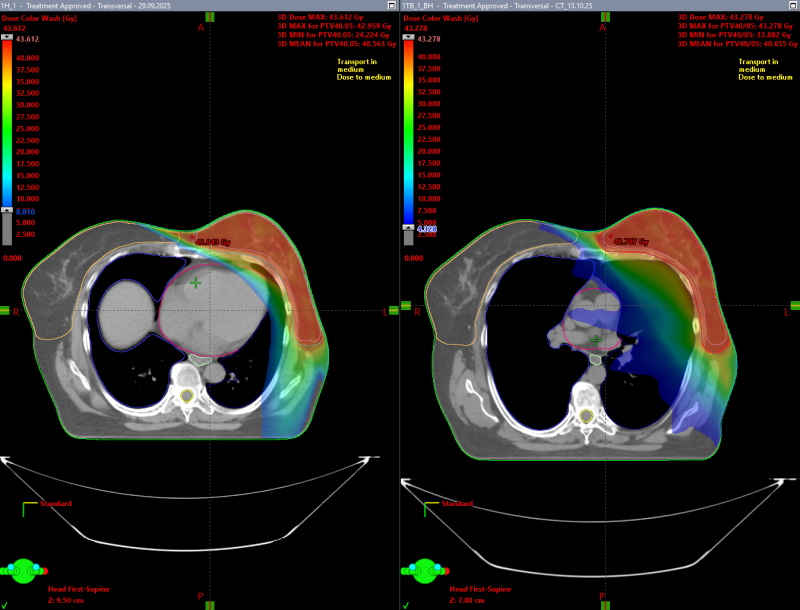

Для оценки эффективности методики в центре был проведён сравнительный анализ на группе пациентов. Каждому из них выполнены два вида КТ-разметки:

- на свободном дыхании;

- с задержкой дыхания (вдох, используемый для синхронизации).

Медицинскими физиками были созданы два варианта планов облучения, основанные на данных обеих разметок. Сравнение показало:

- статистически значимое снижение дозы на сердце при использовании методики дыхательной синхронизации;

- улучшение распределения дозы в зоне интереса без увеличения нагрузки на окружающие ткани.